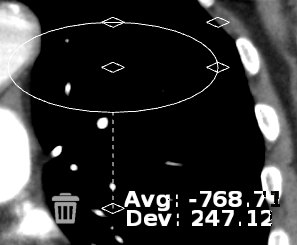

Annotáció törléséhez:

Kattintson duplán az annotáción

Válassza a Törlés ![]() ikont

ikont

A Hounsfield annotációs eszköz létrehoz egy vizsgált területet, és kiszámítja annak átlagos pixelértékét és szórását.

A képre rajzolt alapértelmezett vizsgált terület egy teljes kör. ROI átméretezése során a teljes kört a sarkakon található fogópontokkal tarthatja fenn

A középső megfogási ponttal  mozgathatja az ROI-t a képen, a többivel pedig nyújthatja vagy keskenyítheti.

mozgathatja az ROI-t a képen, a többivel pedig nyújthatja vagy keskenyítheti.